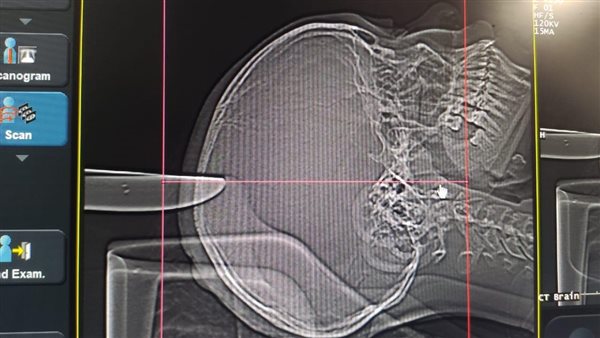

وكان تبين من إجراء الأشعة اختراق السكين لعظام الجمجمة والمخ، وتمت إزالة السكين واستكشاف الجرح والذي أظهر وجود اختراق السكين للأغشية السحائية وإحداثه نزيفا بالمخ.